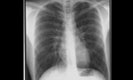

40 jähriger Patient Triathlon Sportler. Bei einem Wettkampf muss der Patient wegen akut auftretender Dyspnoe nach dem Schwimmen, die Disziplin des Fahrradfahrens abbrechen und kann den Triathlon nicht beenden. Einlieferung in die Notaufnahme des nächstliegenden Spital. Ihre Diagnose? Weitere radiologische Diagnostik notwendig?